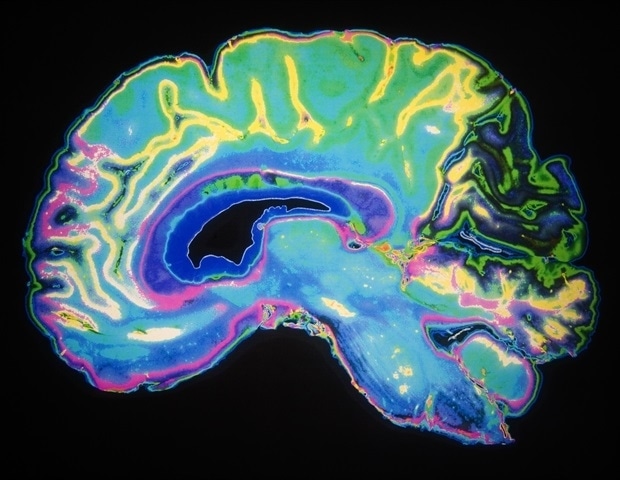

Ανάμεσα στους καρκινικούς εγκεφαλικούς όγκους, το αστροκυττώμα είναι από τους πιο συνηθισμένους, αλλά και τους πιο επικίνδυνους. Η χειρουργική αφαίρεσή του είναι συχνά περίπλοκη, καθώς τα καρκινικά κύτταρα εισβάλλουν στο υγιές γύρω ιστό. Σε επτά από τους δέκα ασθενείς, η ασθένεια επανεμφανίζεται μετά την αρχική θεραπεία, με την πρόγνωση να είναι ιδιαίτερα απογοητευτική, καθώς το ποσοστό επιβίωσης στα πέντε χρόνια φτάνει μόλις το 5%. Τώρα, η ομάδα ερευνητών με επικεφαλής τη νευροχειρουργό Ιζαμπέλ Χοστετλέρ σκοπεύει να βελτιώσει τις πιθανότητες κέρδους απ’ αυτόν τον τύπο όγκου με μια νέα, ήπια θεραπευτική προσέγγιση βασισμένη στις νανοζύμες.

Στην τρέχουσα πρακτική, η θεραπεία των αστροκυτωμάτων βασίζεται σε έναν συνδυασμό χειρουργείου, ακτινοθεραπείας και χημειοθεραπείας. Ωστόσο, η τοποθεσία του όγκου, μέσα στον εγκέφαλο, καθιστά δύσκολη την επίτευξη αποδοτικής φαρμακευτικής παρέμβασης, καθώς η αιματοεγκεφαλική δικλείδα, που προστατεύει τον εγκέφαλο από επιβλαβείς ουσίες, εμποδίζει την πρόσβαση ορισμένων θεραπειών. Ο Γκακάμο Ρέινα και οι συνεργάτες του από το εργαστήριο Νανοϋλικών Υγείας στο Σεν Γκάλεν επιθυμούν να παρακάμψουν αυτό το εμπόδιο με μια έξυπνη τακτική: την ανάπτυξη βιοσυμβατών νανοϋλικών, που θα λειτουργούν ως νανοϊατρική, χρησιμοποιούμενα απευθείας κατά τη διάρκεια της χειρουργικής διαδικασίας.

Οι νανοζύμες, που είναι νανοϋλικά με ενζυμική δραστηριότητα, είναι σε θέση να ενεργοποιούν ανενεργούς πρόδρομους φαρμάκων ή να παράγουν αντιδραστικές ενώσεις οξυγόνου, καταστρέφοντας έτσι τα καρκινικά κύτταρα. Η μικρή τους διάσταση τους επιτρέπει να διεισδύουν σε βάθος στους ιστούς και να πλήττουν κακοήθη κύτταρα μέχρι και αρκετών χιλιοστών μακριά. Η δυνατότητα ενεργοποίησης τους μέσω κοντινού υπέρυθρου φωτός προσφέρει επιπλέον δυνατότητες ελέγχου της δόσης, μειώνοντας έτσι τις πιθανές παρενέργειες της θεραπείας.